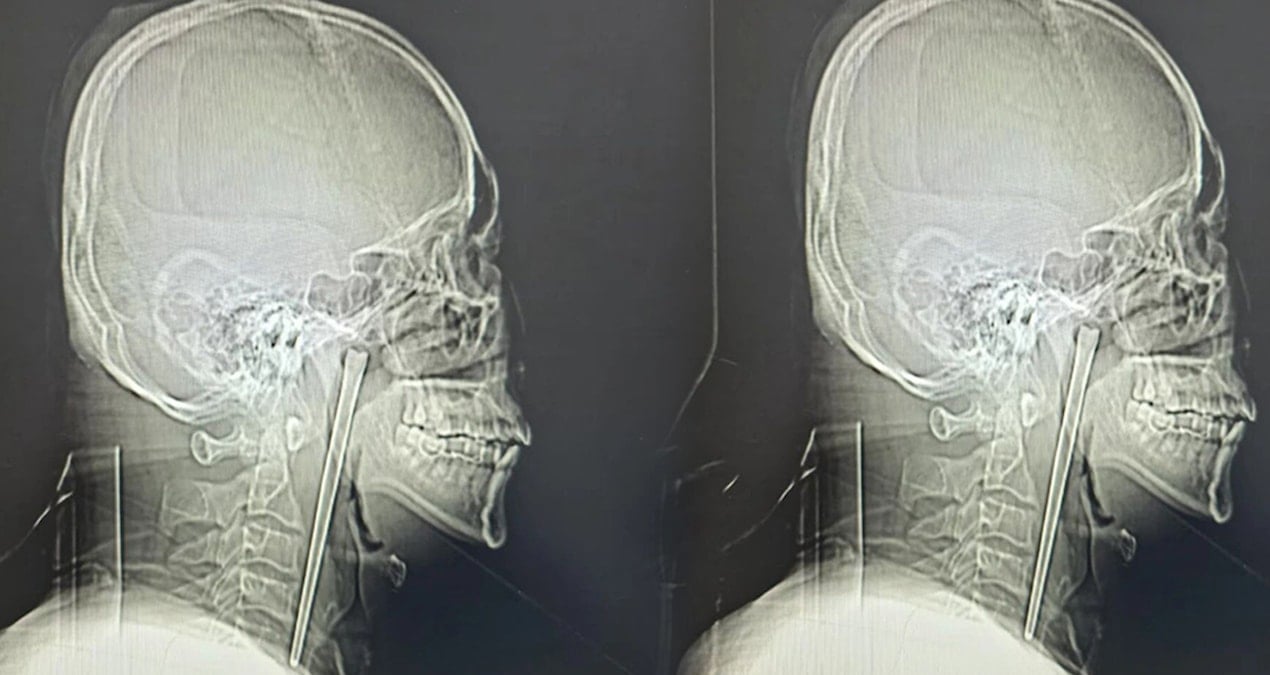

Tartışma esnasında, söz konusu üç genç, polis memuru H.Ç.’ye saldırarak burnuna vurdu. Olayın ardından kaçmaya başlayan şüpheliler, polis memurunun ‘Dur’ uyarısına rağmen kaçmayı sürdürdü. Bunun üzerine H.Ç., havaya uyarı ateşi açtı ancak bu esnada kurşunlardan biri, kaldırımda bulunan 48 yaşındaki berber Hakan B.’ye isabet etti. Hakan B., polisin uyarı ateşi sonucu göğsünden vurularak ağır yaralandı.

Olayın ardından çevredeki vatandaşların ihbarı üzerine sağlık ve polis ekipleri olay yerine sevk edildi. Sağlık ekipleri, Hakan B.’ye olay yerinde İlk müdahaleyi yaptıktan sonra, ağır yaralı berber, ambulansla Seyrantepe Hamidiye Eğitim ve Araştırma Hastanesi’ne kaldırıldı. Hakan B.’nin sağlık durumunun ciddiyetini koruduğu bildirildi.